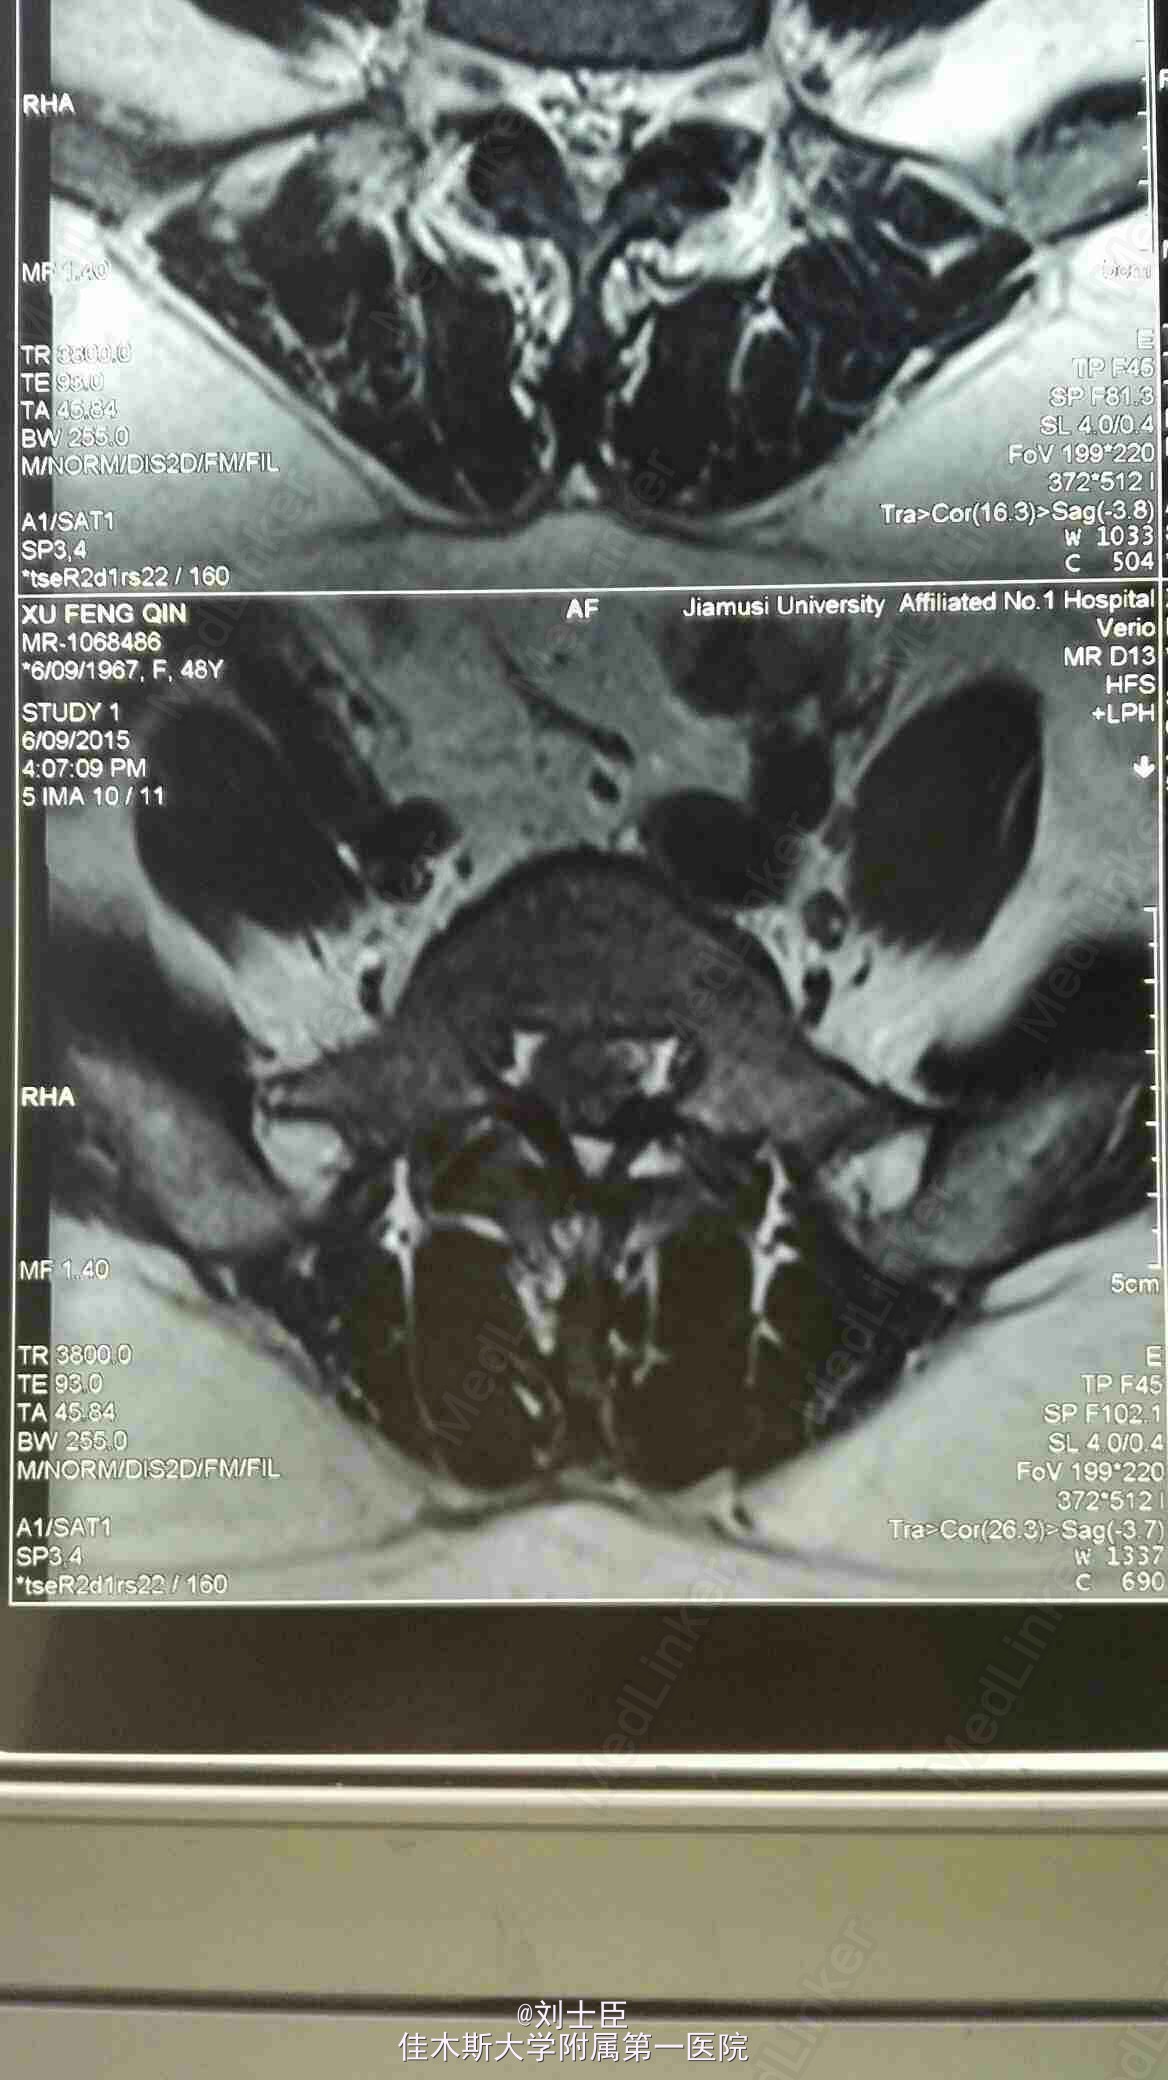

某某,女,43岁。腰痛伴双下肢疼痛1年伴二便失禁7天。

双侧小腿外侧双足及双臀部感觉麻木,双膝反射弱,双踝反射为引出。双下肢肌力进正常。

腰5骶1间盘突出症。马尾综合征。椎间孔镜下游离间盘摘除术纤维环成形术。

病人术后即可刻下地行走自如,直腿抬高实验阴性。3天后拔出尿管,二便正常,双下肢和臀区感觉麻木减轻。